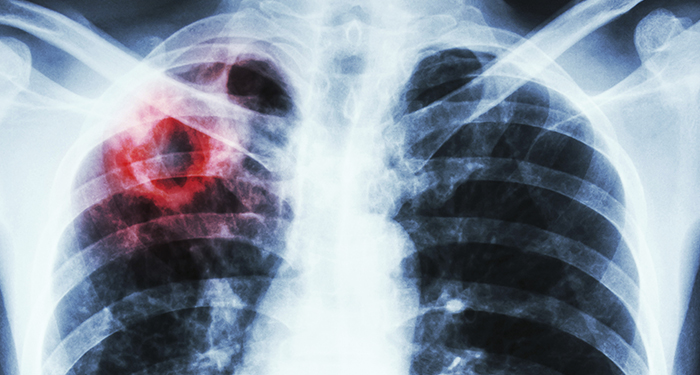

World Tuberculosis Day – March 24, 2019

On this World Tuberculosis (TB) Day, CIHR- Institute of Infection and Immunity reaffirms its commitment to eliminating this deadly disease. TB is both preventable and treatable, yet the global burden of the disease remains high. While the overall rate of TB in Canada is one of the lowest in the world, individuals without access to quality health care, food security, housing and other social determinants of health are among the most susceptible. In Canada, TB disproportionately affects Indigenous Peoples and foreign-born individuals.

TB continues to be among the leading cause of death due to infectious disease globally. We need to accelerate our research efforts to develop better prevention, early diagnosis and treatment methods. CIHR is committed to addressing these needs to improve the health of Canadians and make a difference globally.